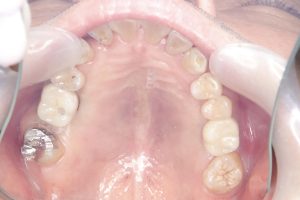

午後は、秋オペした同世代の方

デンサーリフト、いわゆるソケットリフトした方のセットあり

左右共に2か月で終了💪

生活の質の向上 Q.O.Lを下げない為には出来るだけ

早く噛めるようにするのがプロ!